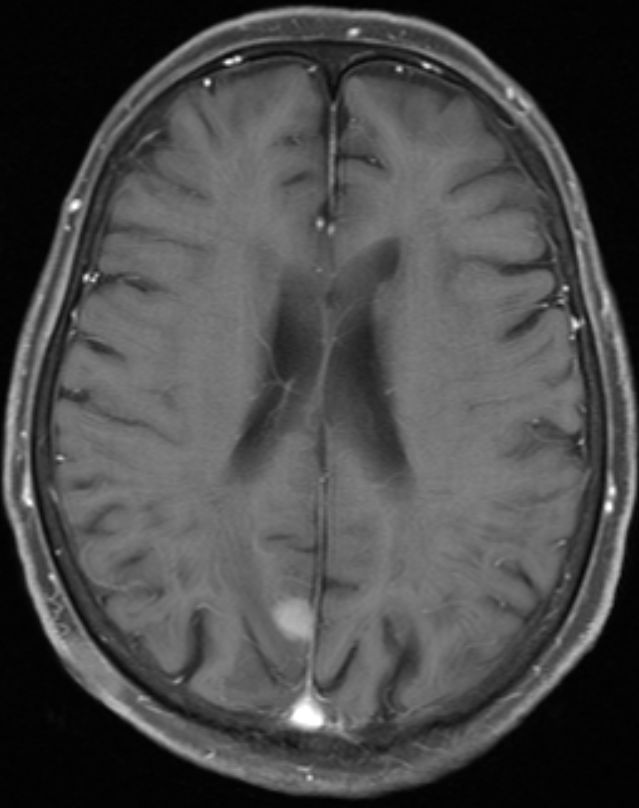

84-jährige Frau, die vor 3 1/2 Jahren einen 35 mm großen derben

Rektumpolypen entwickelte. Die submuköse Exzision ergab ein malignes Melanom

mit Infiltration der tiefen Muskulatur und Ummauerung größerer Gefäße. BRAF+.

Vor 2 Jahren Rektumschleimhau-Rezidiv und Metastase rechts pararektal:

anteriore Rektumresektion. Vor 4 Monaten Lungenmetastase und singuläre

Hirnmetastase re occipital. Dabrafinib + Trametinib nach 2 Zyklen wegen

Hepatotoxizität und Hautausschlag abgebrochen. Jetzt: RT der Hirnmetastase

und des pararektalen Tumors. |